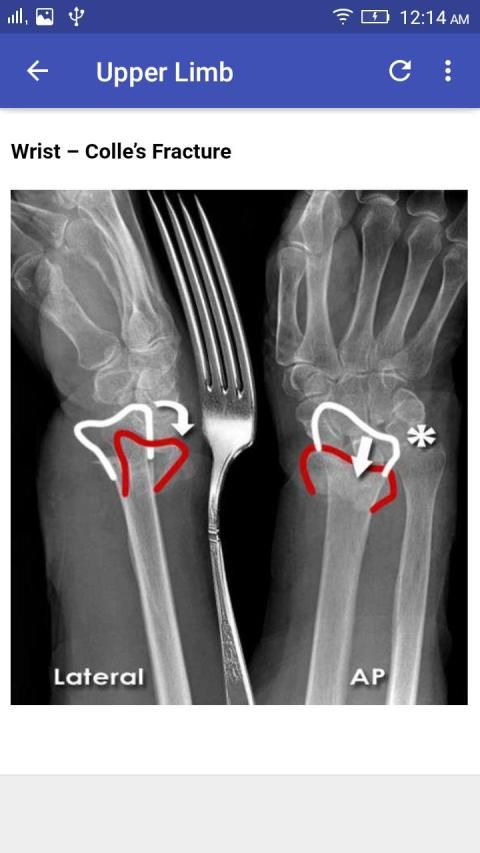

Interpretation of Skull, paranasal sinuses, orbit, chest, abdomen, urogenital tract (pelvis), and musculoskeletal x-rays.